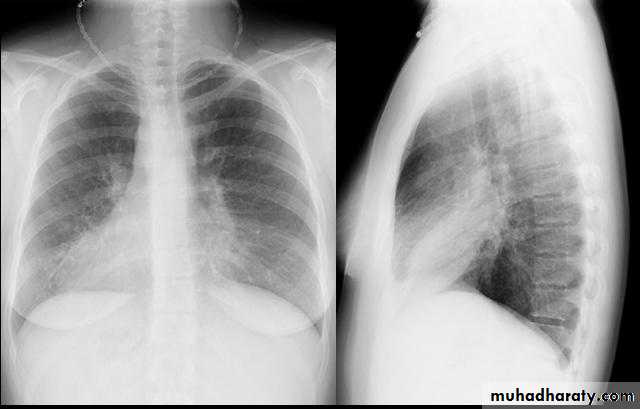

• 2-Plain CXR may shows prominent vascular marking .

• 4-Bronchography through giving radio opaque dye through the bronchoscope & into bronchial tree ,now replaced completely by CT.

• 5-Chest CT is the single non invasive tool for both diagnosing &assessing the severity of the disease .